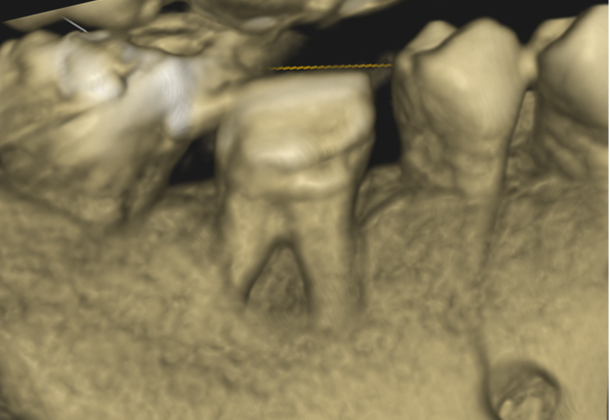

症例1:パーフォレーションリペア症例

(歯の中に大きな穴が空いてしまっているのを埋めて再生を促す治療)

歯に穴が空いていて骨に炎症がある状態 |

CTでも歯の周囲に骨がないのが分かる。 |

人為的根穿孔を起こした部分に感染を起こしており、歯周ポケットが9㎜ありました。 ラバーダム防湿とマイクロスコープを使用して丁寧に治療を行いました。 殺菌性があり歯を補強することのできるMTAという根管充填材料を使用して、歯周ポケットは2㎜に改善しました。 |